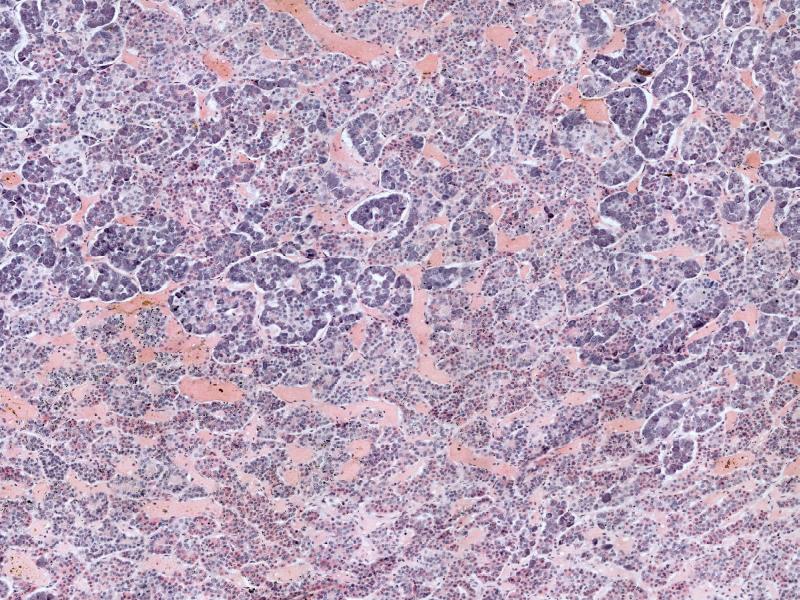

Adrenal glands

Capsule

Cortex - how many zones?

Medulla

Hormones of each?